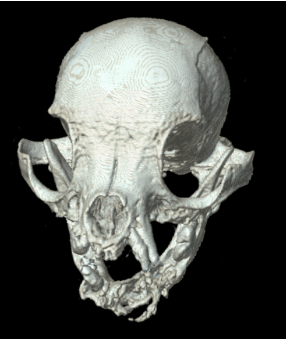

뼈 구조 3D 평가

골절·변형·병변 범위를 입체적으로 확인하는 데 도움됩니다.

(참고사진 : 두개골/안면 골병변이 의심되는 환자의 3D CT 영상)